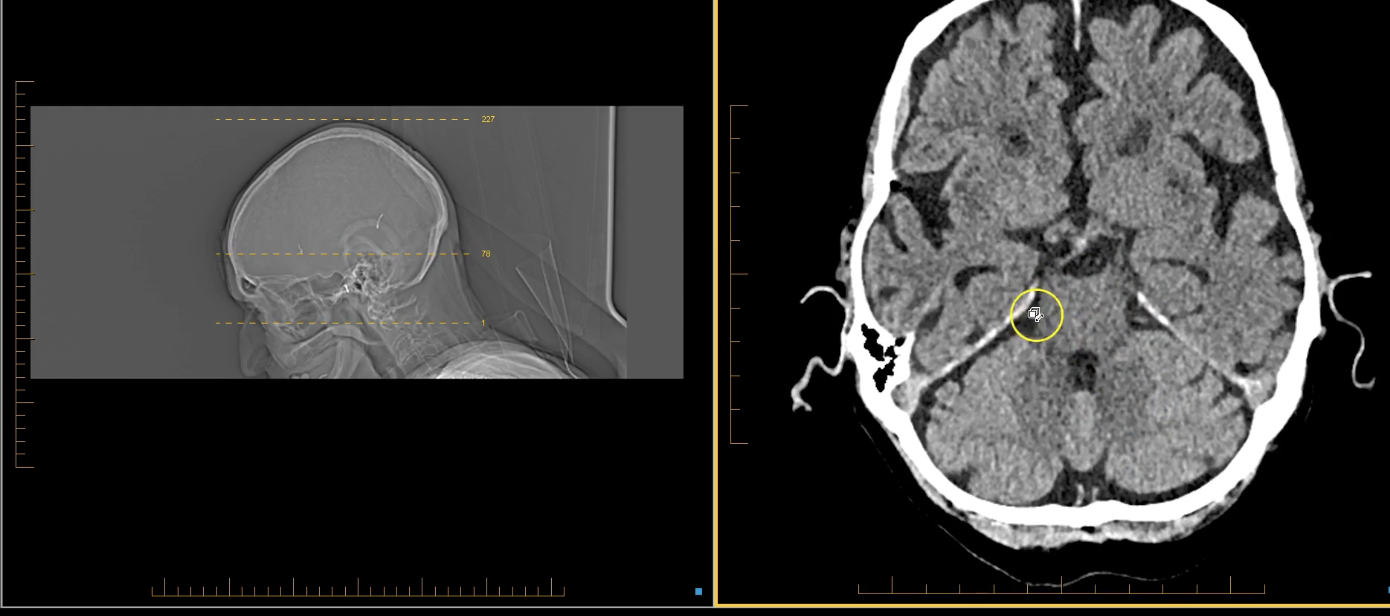

term image

pineal gland- hyperdense. part of endocrine system. secrenes melatonin